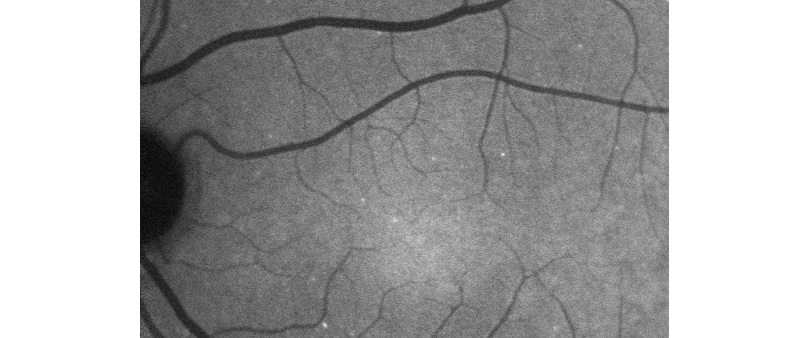

The Wellcome-funded diagnostic – developed by researchers at University College London (UCL) and the Western Eye Hospital – allows doctors to see individual nerve cell death in the back of the eye.

“Now, for the first time, we have been able to show individual cell death and detect the earliest signs of glaucoma. While we cannot cure the disease, our test means treatment can start before symptoms begin.”